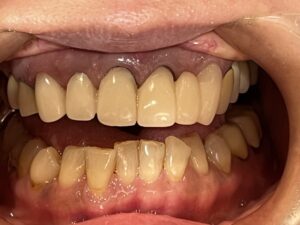

元々、上の前歯に入っている補綴物の状態がこちらです。

歯と歯茎の境が黒くなっているのがわかります。

まずは元々入っている補綴物を外し、仮の歯を入れていきます。

仮歯を入れた状態がこちらです。

そして前歯にフルジルコニアセラミッククラウンを入れた状態がこちらです。

Before After

歯と歯茎の境もなくしっかりとフィットし、綺麗な仕上がりになりました。

笑顔もとても素敵ですね♪